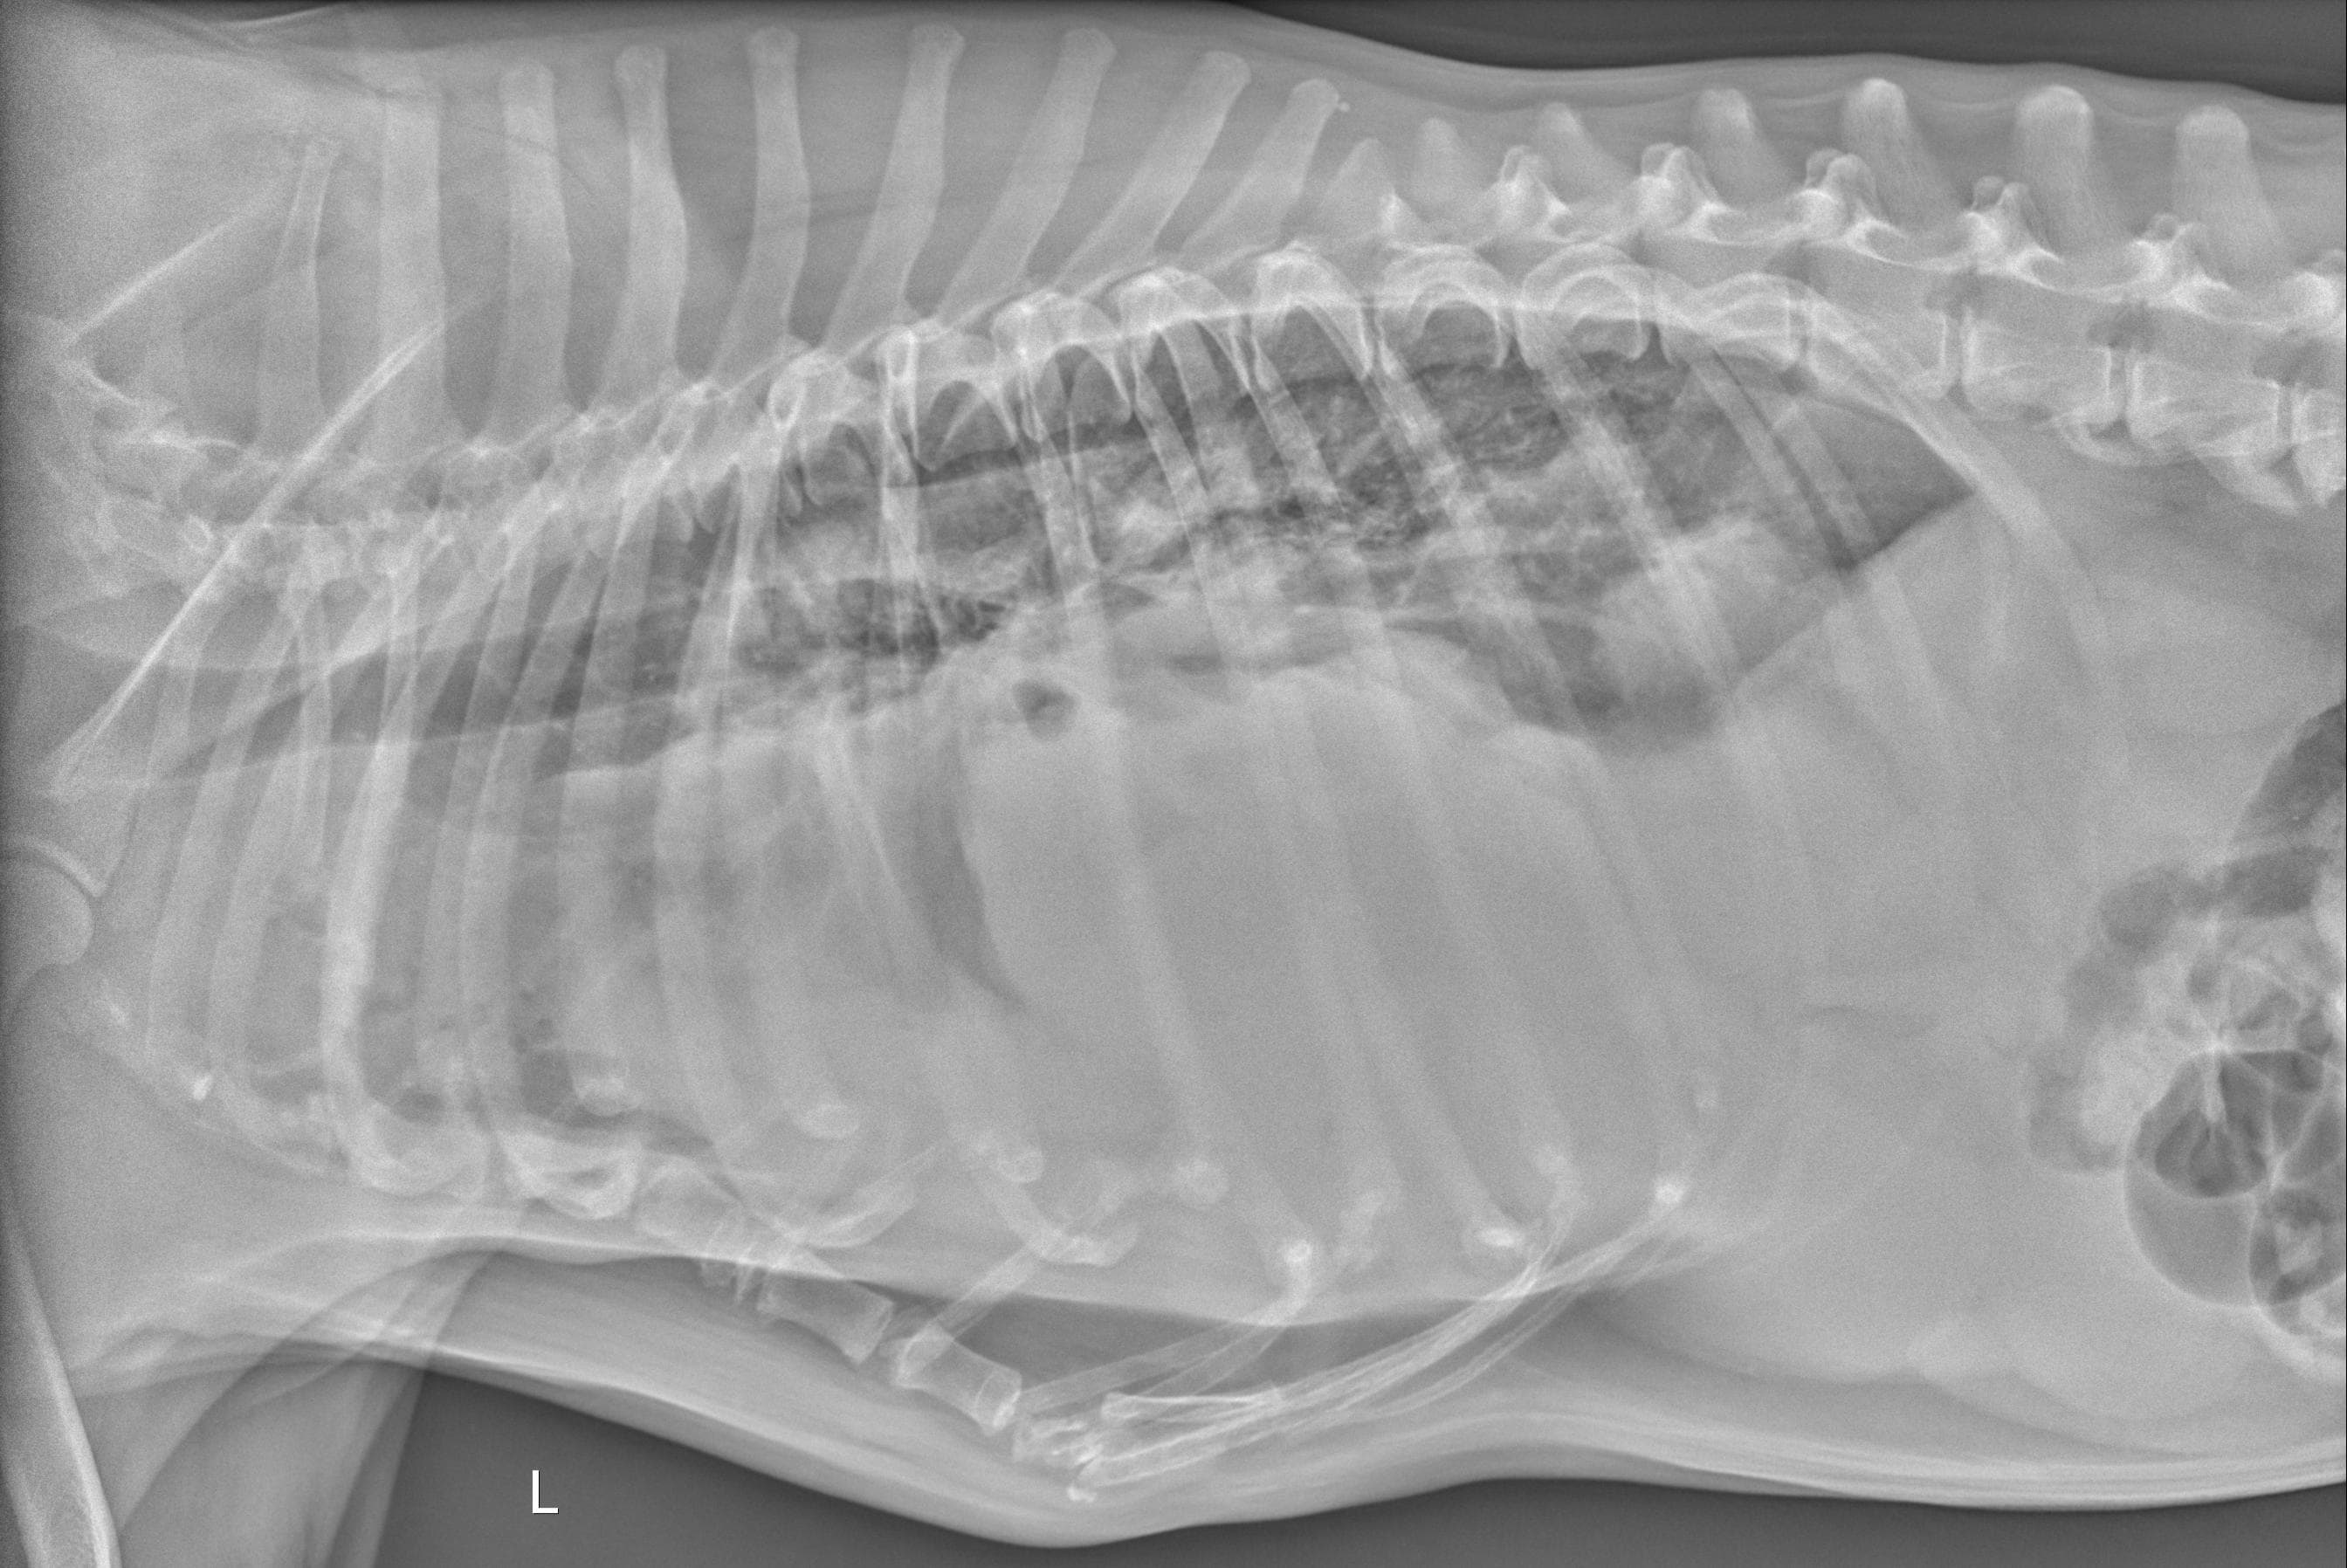

I am in a lot of pain today. My 10yo spayed female dog has had difficulty breathing for about a month or so (getting worse every day) and has lost a lot of weight, although she eats and drinks normally. Vet found severe pleural effusion and drained it (a large dog food bowl worth) and it was bloody, not a good sign. Attached are the x-rays taken today and I would like to know what your opinion is on prognosis and whether it would be wise and humane to pursue this or I should let her go.

Poor Xica! I'm so sorry that she's sick, and that you're in the position of having to consider what is best for her right now. This is always a difficult situation. Her x-rays do appear to show very severe pleural effusion. As I'm sure your veterinarian has probably discussed with you, pleural effusion of the type that you have described (bloody fluid) is almost always caused by one of two things: congestive heart failure, or cancer. The amount of fluid in her chest makes it hard to get a good look at the size and shape of her heart, or to determine if there are any obvious tumors in her chest, so it's hard to say which of these possibilities is more likely without additional testing. But unfortunately, even with aggressive treatment, neither of them have a good long-term prognosis. Knowing this, if I were in your position, I believe I would probably decide to let her go rather than pursuing hospitalization, chest tube placement, etc. - these are invasive, uncomfortable procedures that are unlikely to make a significant difference in the outcome for her, because of the severity of her underlying disease. That being said, the decision of when to consider euthanasia is a very personal choice, and one that is different for every pet owner. If you feel that you need to do everything possible, and want to pursue advanced diagnostics to try and get a more specific answer as to what's wrong, there is nothing wrong with this at all - but if you were my client, I would try to gently caution you that her underlying condition will almost certainly be fatal regardless of what you do. I hope you're able to find peace in your decision, whatever it might be.

These xrays show a number of very concerning findings and the weight loss is a confounding factor. Her prognosis is very poor and if draining the chest has not provided significant relief of her symptoms then yes, euthanasia may be the kind option for Xica. Curative treatment is extremely unlikely and if her respiratory symptoms were not completely resolved with draining then medical management is not expected to maintain adequate comfort either. Remember all the good times she has given you and take comfort in your ability to release her from pain and discomfort at the appropriate time